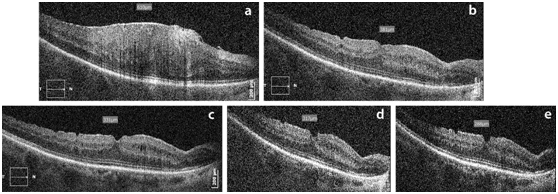

In the OCT examinations, the mean preoperative CMT was 426.1μm (SD 90.9μm). A progressive reduction of the CMT’s mean value was noted at all postoperative time visits. In particular, mean CMT was 340.3μm (SD 75.5μm) at the 1st postoperative month, 307.9μm (SD 57.3μm) at the 6th postoperative month, 280.6μm (SD 50.4μm) at the 1st postoperative year and 268.3μm (SD 40.5μm) at the last follow up visit. Statistically significant reduction was recorded at all postoperative examinations, where P<0.0001. Figure 2 depicts a 68 years old woman with gradual reduction of CMT. Mild cystoid macular oedema (CMO) is observed postoperatively. Foveal contour begins to form better at 6th postoperative month.

Figure 2 Macular OCT of a 68 years old woman with mild postoperative CMO. (a) preoperative CMT at 610μm. Gradual reduction of the CMT at the postoperative examinations. (b) postop 1m: CMT at 381μm, (c) postop 6m: CMT at 331μm, (d) postop 1yr: CMT at 317μm, (e) postop 3 yrs: CMT at 288μm.